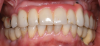

Fig 1. Initial occlusal view of maxillary arch.

Figure 1

Clinical and radiographic examinations were carried out and revealed multiple missing teeth, nonrestorable teeth, periodontal disease, and bone loss (Figure 1 and Figure 2). The final treatment plan that was then proposed to and accepted and signed by the patient included extraction of all remaining teeth in the maxilla, delivery of a provisional fixed restoration supported by six transitional implants, bilateral sinus augmentation, placement of eight to 10 conventional implants, and an implant-supported porcelain-fused-to-metal or hybrid (screw-retained) restoration. For the mandible, the plan included extraction of teeth Nos. 29 and 32 and placement of implants in sites Nos. 18, 19, 20, 29, 30, and 31, with three splinted implant-supported fixed crowns on each side. The patient, however, decided to proceed only with the maxillary restoration and have the mandibular implants and restorations done in private practice.